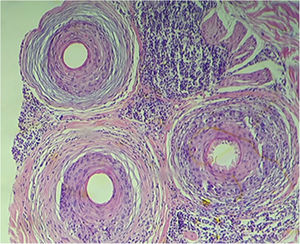

Exame histopatológico de couro cabeludo, folículo piloso (istmo), Hematoxilina & eosina, 100×. Alopecia cicatricial com fibrose concêntrica perifolicular, agressão linfocítica ao epitélio folicular e presença de corpos apoptóticos. A região do infundíbulo e do bulbo não apresentava inflamação